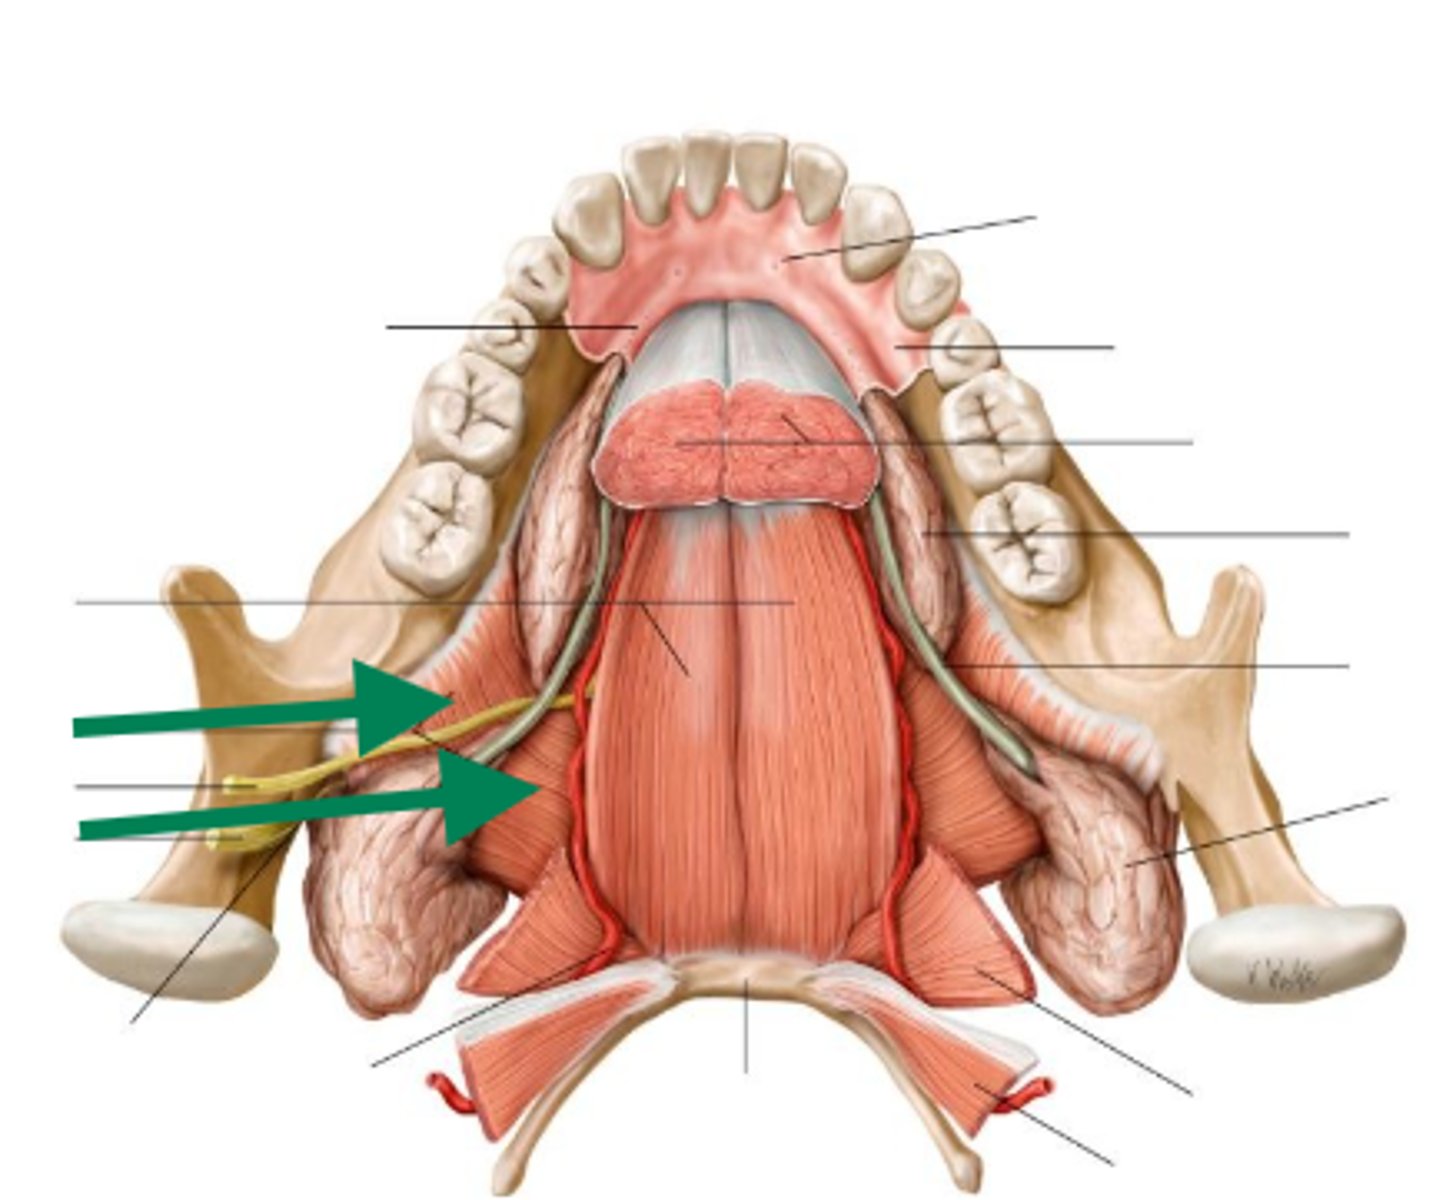

lingual nerve

lingual nerve

lingual nerve

inferior alveolar nerve

inferior alveolar artery

medial pterygoid

mental nerve

lingual nerve

buccal artery

buccal nerve

mandibular foramen